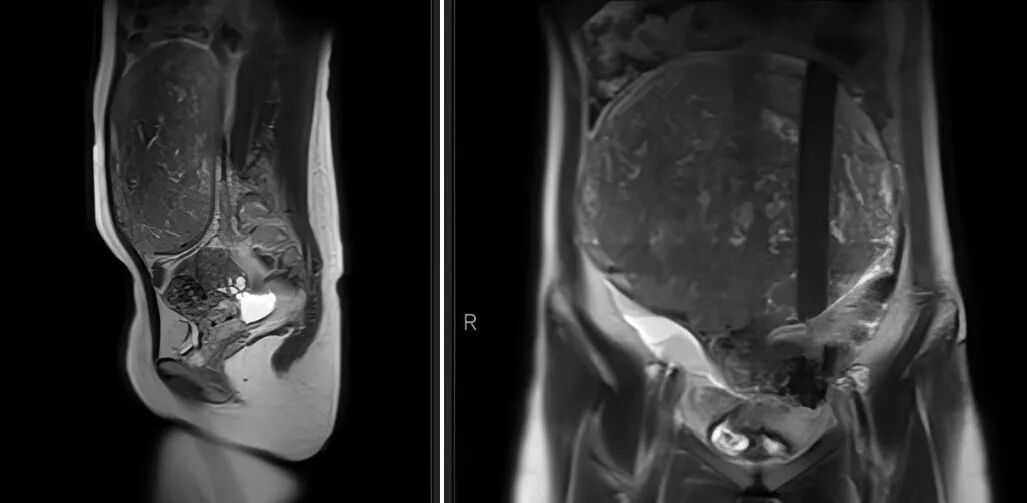

消化内科医生查体时发现,她的腹部有一个巨大的包块。进一步做全腹+盆腔CT提示:盆腹腔巨大占位,大小约22×20cm——一个比足球还大的肿瘤!由于肌瘤体积庞大,已经占据了盆腹腔大部分空间,压迫周围脏器,严重影响日常生活。若再拖延,还可能导致贫血、恶变,甚至影响未来生育。

考虑到小李年仅21岁,有强烈的保留子宫、维持生育能力的意愿,该院妇科团队高度重视,立即组织多学科会诊,反复研讨手术方案。最终决定采用经腹子宫肌瘤剔除术——既能彻底剥离巨大肌瘤,又能最大限度减少对子宫肌层的损伤。

手术当天,在麻醉团队的密切配合下,胡静主任医师、刘高伟副主任医师凭借精湛技术,小心翼翼切开腹部,精准分离肌瘤与周围正常组织,成功将这颗重达数斤的巨大肌瘤完整剔除。手术过程顺利,出血极少,子宫得以完整保留。